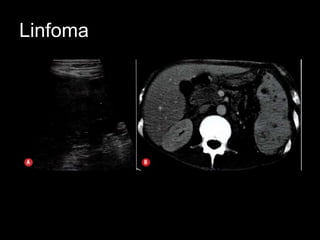

Linfoma

• Esplenomegalia sem massas

• Padrão infiltrativo difuso

• Massa múltiplas: diâmetro 1,0-10,0 cm

• Grande massa focal solitária

– Hipoecóica

Linfoma • Esplenomegalia semmassas • Padrão infiltrativo difuso • Massa múltiplas: diâmetro 1,0-10,0 cm • Grande massa focal solitária – Hipoecóica